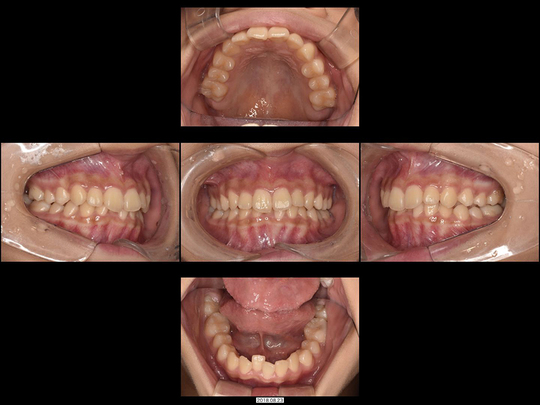

Wさん 10代 女性

矯正前

矯正後

下の前歯がガタガタしていて、上の前歯の裏側に当たって痛い、咬みづらいというケースです。

奥歯の高さを高くして少し口が開いたような状態にして咬み合わせを作ると同時に、前歯を歯ぐき方向に垂直に押し込みながら傾斜移動させる治療計画を立案しました。マウスピース矯正では咬むことで奥歯に沈む力がかかってしまい奥歯の高さを高くすることが難しいため、ワイヤー矯正を選択しています。

治療の期間・回数

16か月、20回

​費用

660,000円

リスクや副作用:歯とあごのバランスによってはご自身の歯を抜く場合があります。まれに歯の根が短くなる可能性があります。装置装着後、痛みを感じることがあります(歯が動く正常な反応なので心配ありません)。頬の粘膜・唇・舌などに、口内炎ができることがあります。歯周病等で歯ぐきが下がっている方は、歯を動かすことでさらに歯ぐきが下がる可能性があります。重なっていた歯がきれいに並んだことで歯ぐきと両隣の歯との間に三角形の隙間ができる可能性があります。